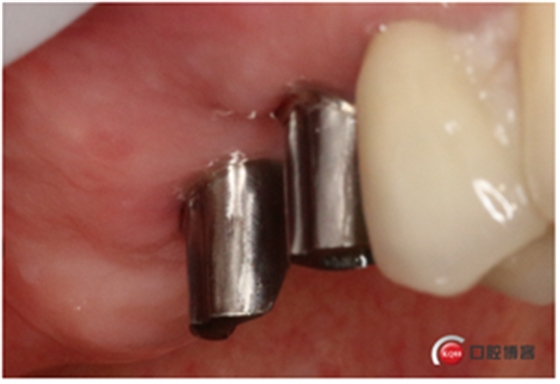

同期植入植體。